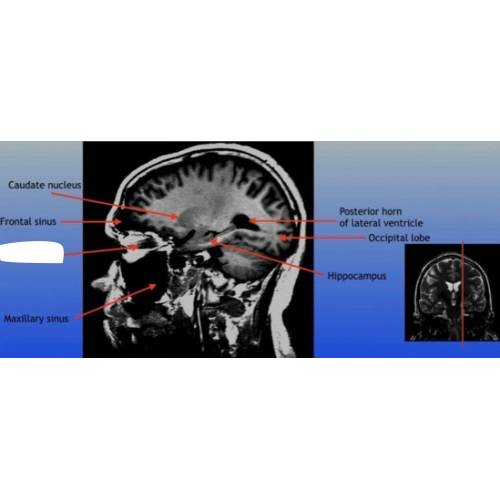

Caudate Nucleus

A C-shaped structure within the brain's basal ganglia, involved in various functions including motor control and learning.

Frontal Sinus

A paired cavity located within the frontal bone, above the eyes, that plays a role in sinus drainage and resonance of the voice.

Maxillary Sinus

A paired cavity located within the maxilla, situated below the eyes, that contributes to sinus drainage and helps lighten the weight of the skull.

Posterior Horn of Lateral Ventricle

The posterior part of the lateral ventricle, involved in the production and circulation of cerebrospinal fluid within the brain.

Hippocampus

A critical region in the brain associated with memory formation and spatial navigation, located in the medial temporal lobe.